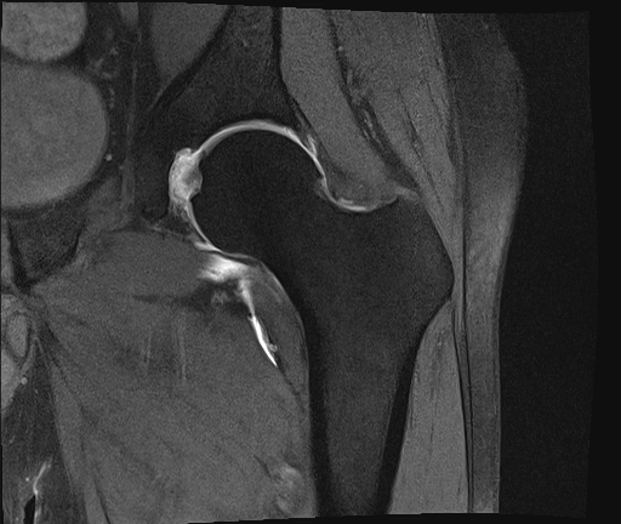

Diagnostic Testing. The evaluating clinicians obtained AP (Figure 1) and lateral (Figure 2) radiographs as well as magnetic resonance arthrogram (MRA) images of the left hip (Figures 3 and 4).

Figure 3. The Coronal T2 MRI with arthrogram is shown.